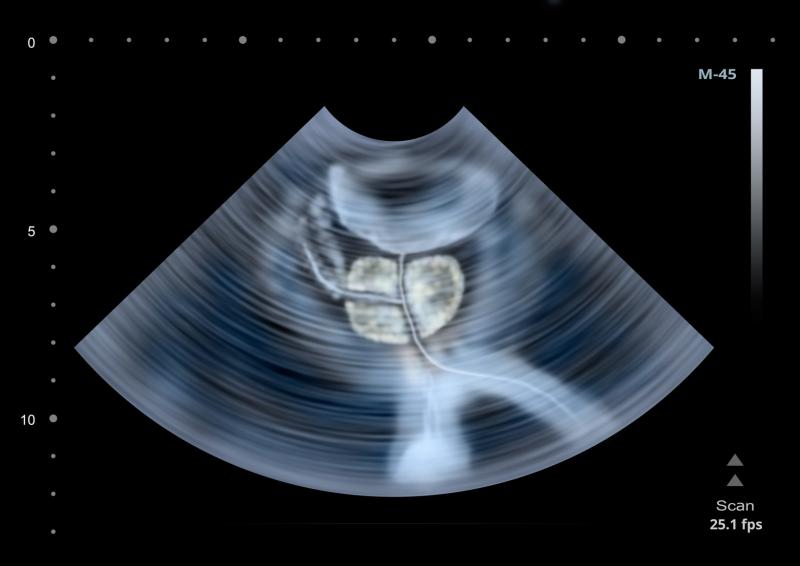

The total number of vapour treatments to each lobe of the prostate was determined by length of prostatic urethra and included middle lobe treatment following physician discretion.

“[Water vapour thermal therapy] is a versatile therapy, providing successful treatment to obstructive lateral and middle lobes,” the researchers said.